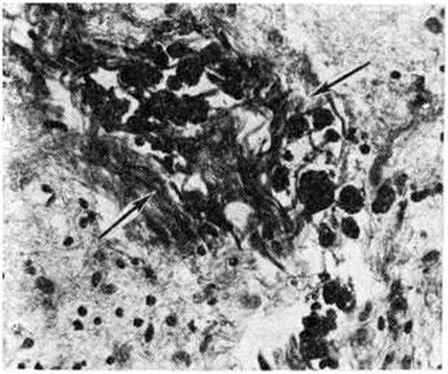

Геморрагический инсульт, как правило, возникает при заболеваниях, протекающих с повышенным артериальное давление. Это обусловлено тем, что сосудистые кризы (смотри полный свод знаний), характерные для гипертонической болезни (смотри полный свод знаний) и артериальной гипертензии (смотри полный свод знаний Гипертензия артериальная), приводят к морфологический изменениям стенок внутримозговых сосудов с нарушением их проницаемости — плазматическому пропитыванию (рисунок 1), некрозам (рисунок 2), образованию микроаневризм (рисунок 3) и их разрывам. Разрыв врождённых артериальных и артериовенозных аневризм может протекать на фоне нормального давления. Преимущественная локализация и характер геморрагий определяются особенностями ангиоархитектоники различных отделов мозга. При гипертонической болезни наиболее тяжёлым изменениям подвергаются сосуды подкорковых узлов и зрительного бугра. Это объясняется отхождением глубоких ветвей под прямым углом от средней мозговой артерии, являющейся продолжением внутренней сонной артерии, и незначительным числом анастомозов сосудов в этой области. В связи с этим на вскрытии кровоизлияния наиболее часто (40%) обнаруживаются в подкорковых узлах с распространением в прилежащее белое вещество (так называемый латеральные кровоизлияния, то есть расположенные латерально от внутренней капсулы, рисунок 4). Второе место по частоте (16%) занимают обширные кровоизлияния, разрушающие подкорковые узлы, внутреннюю капсулу, зрительный бугор (так называемый смешанные кровоизлияния — рисунок 5). Кровоизлияния в зрительный бугор (так называемый медиальные — рисунок 6) составляют 10%, в мозжечок — 6—10%, в мост мозга — 5% от общего числа внутримозговых геморрагий. Кровоизлияния только в белое вещество полушарий мозга встречаются крайне редко. Подразделение полушарных кровоизлияний на латеральные, медиальные и смешанные имеет особое значение в связи с хирургическим лечением геморрагического Инсульт.